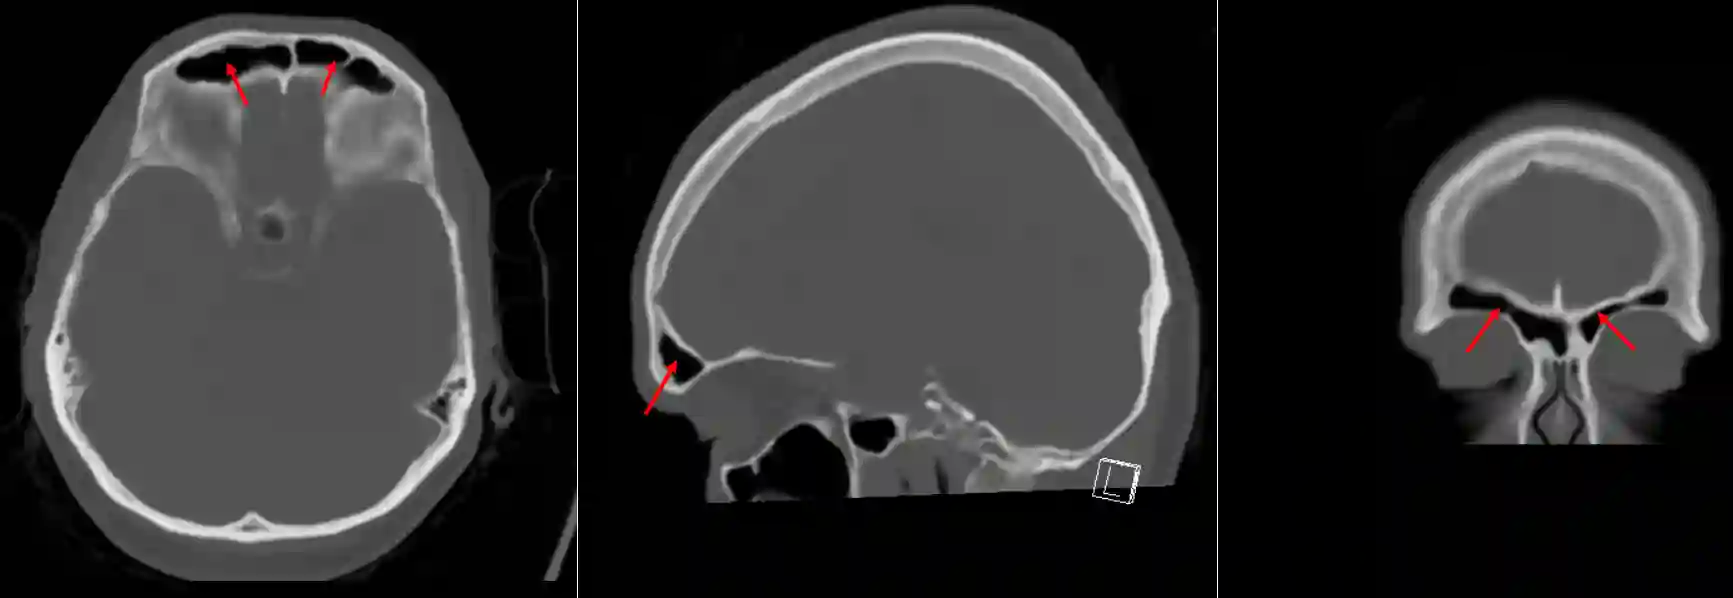

Ansicht des Sinus frontalis eines gesunden Erwachsenen in allen drei Ebenen im CT.